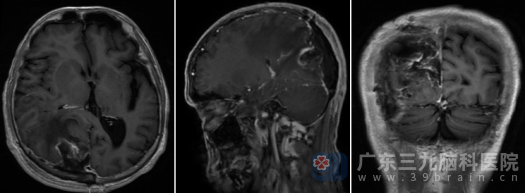

术后病理证实为脑膜瘤。复查MR显示肿瘤切除彻底,周围受压脑组织逐步复位。令人欣喜的是,王老先生恢复神速,术后不久即意识清醒,头痛消失,四肢活动自如。出院时,他紧握医护人员的双手:“是你们把这‘要命的东西’拿走了,我现在感觉轻松多了!”